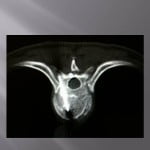

In case of lytic tumoral lesion invading the posterior wall.

The major risk is compression of the spinal roots by the cement. An excellent radio-opacity of the cement is fundamental to perfectly limit its position and its diffusion under continuous scopic control.

We position the trocar at the level of the most anterior portion of the tumor and cross the adjacent bone. We slowly inject a few drops of cement at the level of the vertebrae not invaded, then as the cement is getting more dense, we withdraw while injecting cement.

The lesion must be filled as much as possible. An bilateral entrance way can be very useful for an optimal filling. In case of a pedicular contact, the withdrawal of the trocar is performed slowly while injecting the rest of the very thick cement little by little to create a bone bridge under scopic guidance. The risk to reach nervous root is important by extension in the foramen, a perfect control of the move s compulsory to avoid nervous complications.